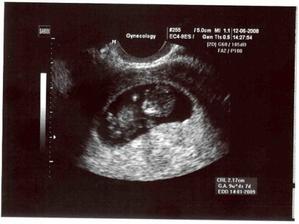

12.6. proběhnul další ultrazvuk, tentokrát to nastávající mamča pěkně obrečela a do toho se s paní doktorkou smála, co tam ten sněhuláček dělal za alotria 🙂) A máme už průkazku! 🙂